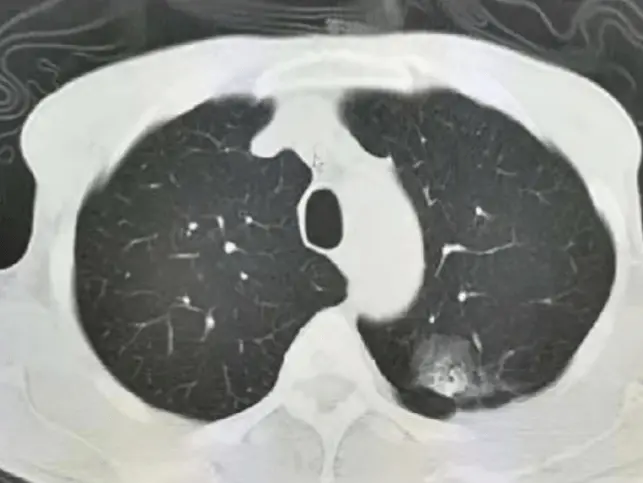

體檢查出7毫米肺結(jié)節(jié),中醫(yī)治療3個月消失

來看診的趙女士就是在體檢的時候查出了一個0.7公分的磨玻璃陰影,去了很多個醫(yī)院,而醫(yī)院給出的回答幾乎都是一樣的,那就是目前還小,先等待觀察。

根據(jù)上述CT前后治療對比顯示,左肺上葉一個0.7X0.6公分的磨玻璃陰影,經(jīng)過3個月治療以后,磨玻璃結(jié)節(jié)消失不見了。